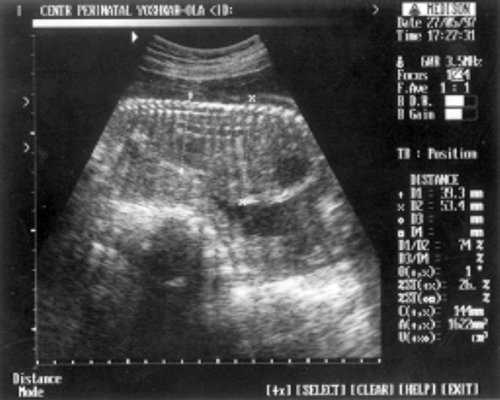

- Кости предплечья = 17,5 мм - 15,5 нед. (рис. 4)

Рис. 4. УЗИ плода - кости предплечья.